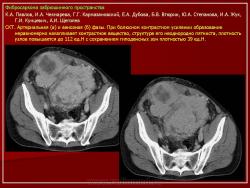

Онкология. Фибросаркома забрюшинного пространства. +

Фибросаркома забрюшинного пространства.